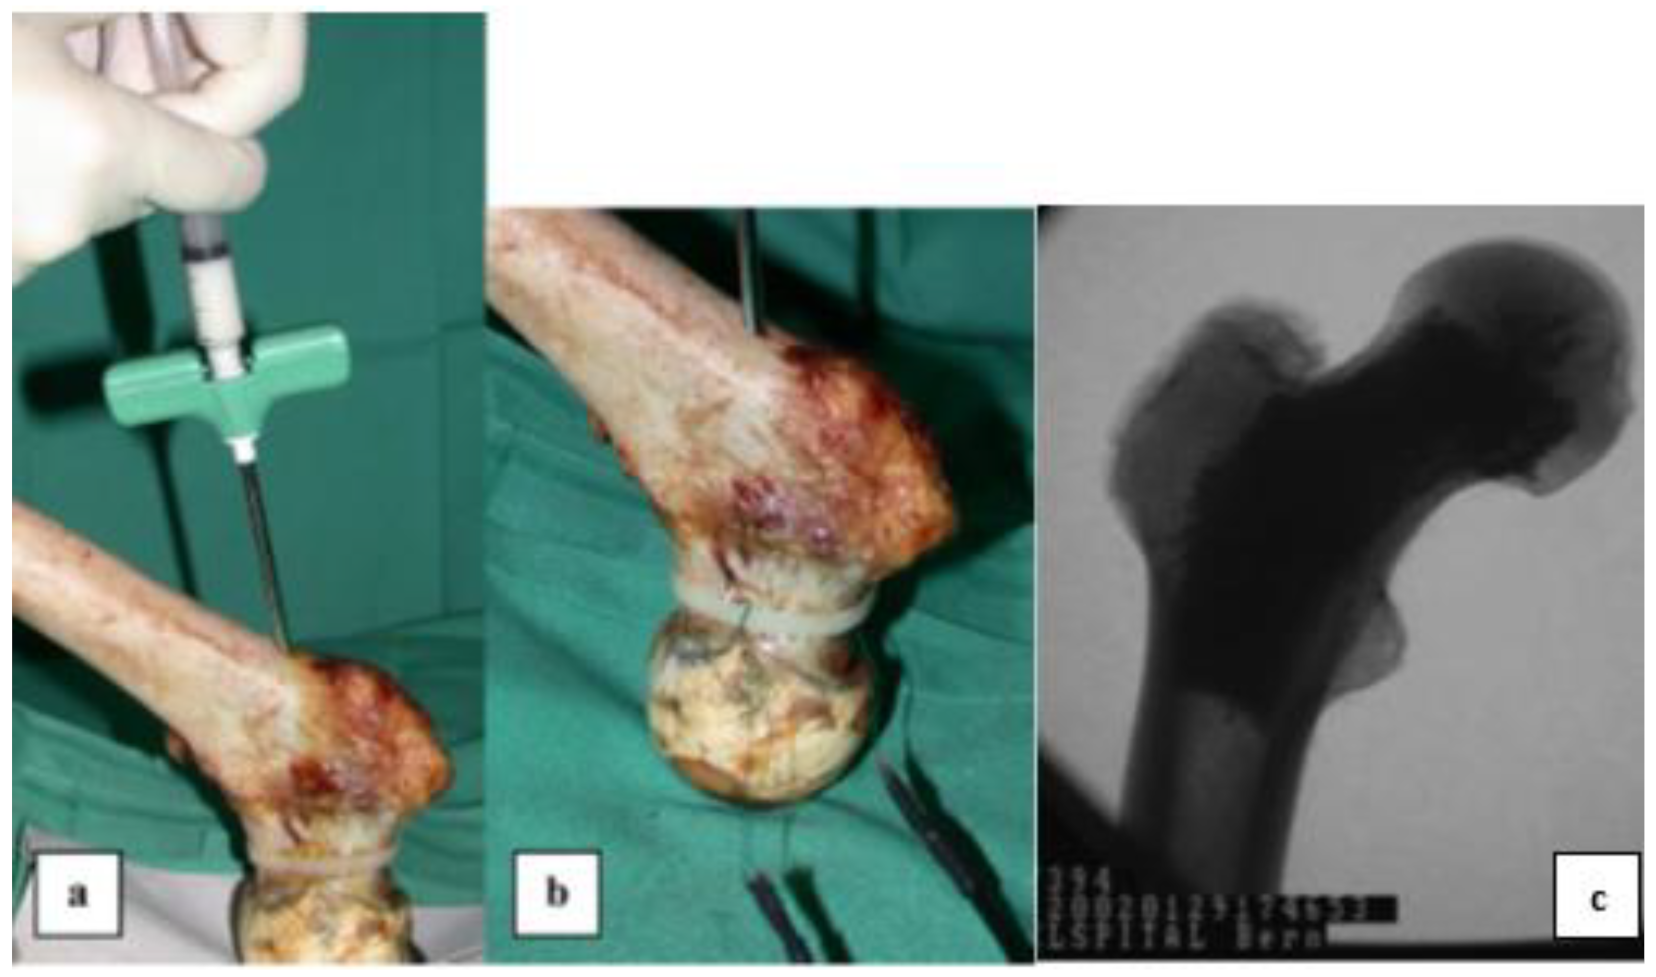

Table 3 shows that, for example, the polymeric cements (mostly PMMA-based) that have been used in kyphoplasty, vertebroplasty, femoroplasty, and arthroplasty for a long time can fix the bone–implant interfaces and treat fractures as well. The radiopacity of such materials can be increased by adding contrast dyes or ceramic second phases (Table 3), conventionally micron-sized and inert bioceramics such as barium sulfate and zirconium dioxide [181,182]. Many examples of such cements have been studied and reviewed in [183,184,185,186]. For instance, an acrylic-based (BIS-GMA) cement in conjunction with bioactive ceramic is highly radiopaque and has good mechanical properties. One such cement, Cortoss®, is currently used in clinical applications for vertebroplasty and is a potentially valuable alternative to PMMA (Simplex® and Spineplex®). The bioactive ceramic (combeite; diameter of ~5–30 μm) component in Cortoss® has been proven to facilitate bone growth directly on the implant. Such a composite can also be used in femoroplasty, a prophylactic cement augmentation of the proximal femur that may reduce fracture risk. Figure 12 shows the examination of Cortoss® in nine pairs of osteoporotic human cadaveric femora (seven males and two females, mean body weight 72 kg, and mean height 169 cm). The good radiological appearance of augmented femora, which is evident in Figure 12c, is mainly due to the addition of inorganic glass-ceramic filler [187,188,189].